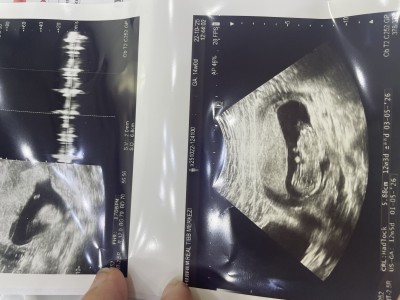

Cinsiyyet tahmini yapa bilirmisiniz kizlar

Gebelik haftası 12+4 haftasindayim cinsiyyet bilmek istiyorum

Erkek Diyorum tamamen kendi hissiyatım. Bide kesen fasulye gibi

Erkek gıbı canm